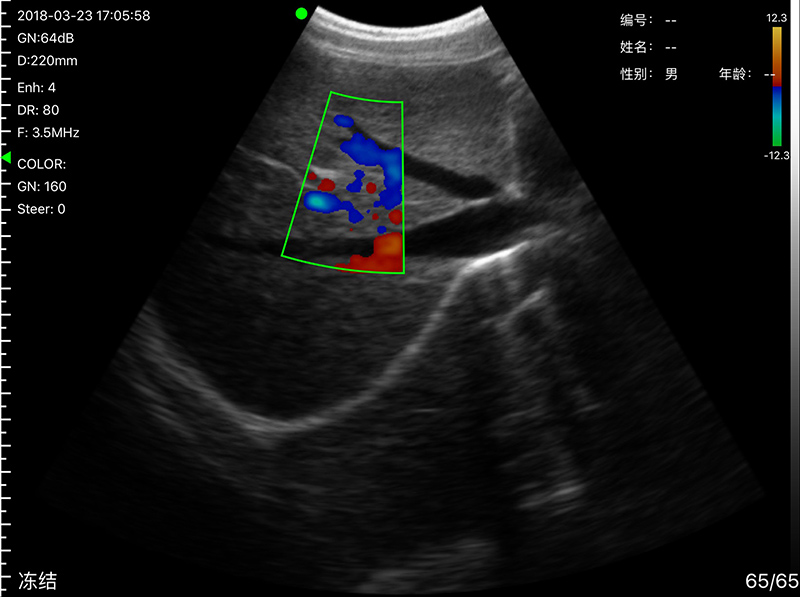

• 显示模式:B、B/M、Color、PW、PDI

• 穿刺辅助功能:平面内穿刺引导线功能,平面外穿刺引导与血管自动测量功能,针尖显影增强功能